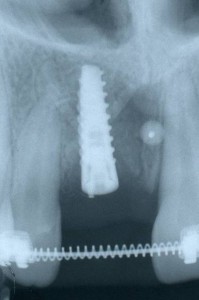

Questo è un caso di implantologia in zona estetica, che ha previsto anche la rigenerazione dell’osso e della gengiva mancante intorno all’impianto.

Questo è un caso di implantologia in zona estetica, che ha previsto anche la rigenerazione dell’osso e della gengiva mancante intorno all’impianto.

Il risultato è stato particolarmente soddisfacente sia per noi che per il paziente.

La MIS Implants, Casa produttrice degli impianti che utilizziamo nel nostro studio ci ha onorato della pubblicazione sul proprio sito, con una presentazione interattiva molto bella.